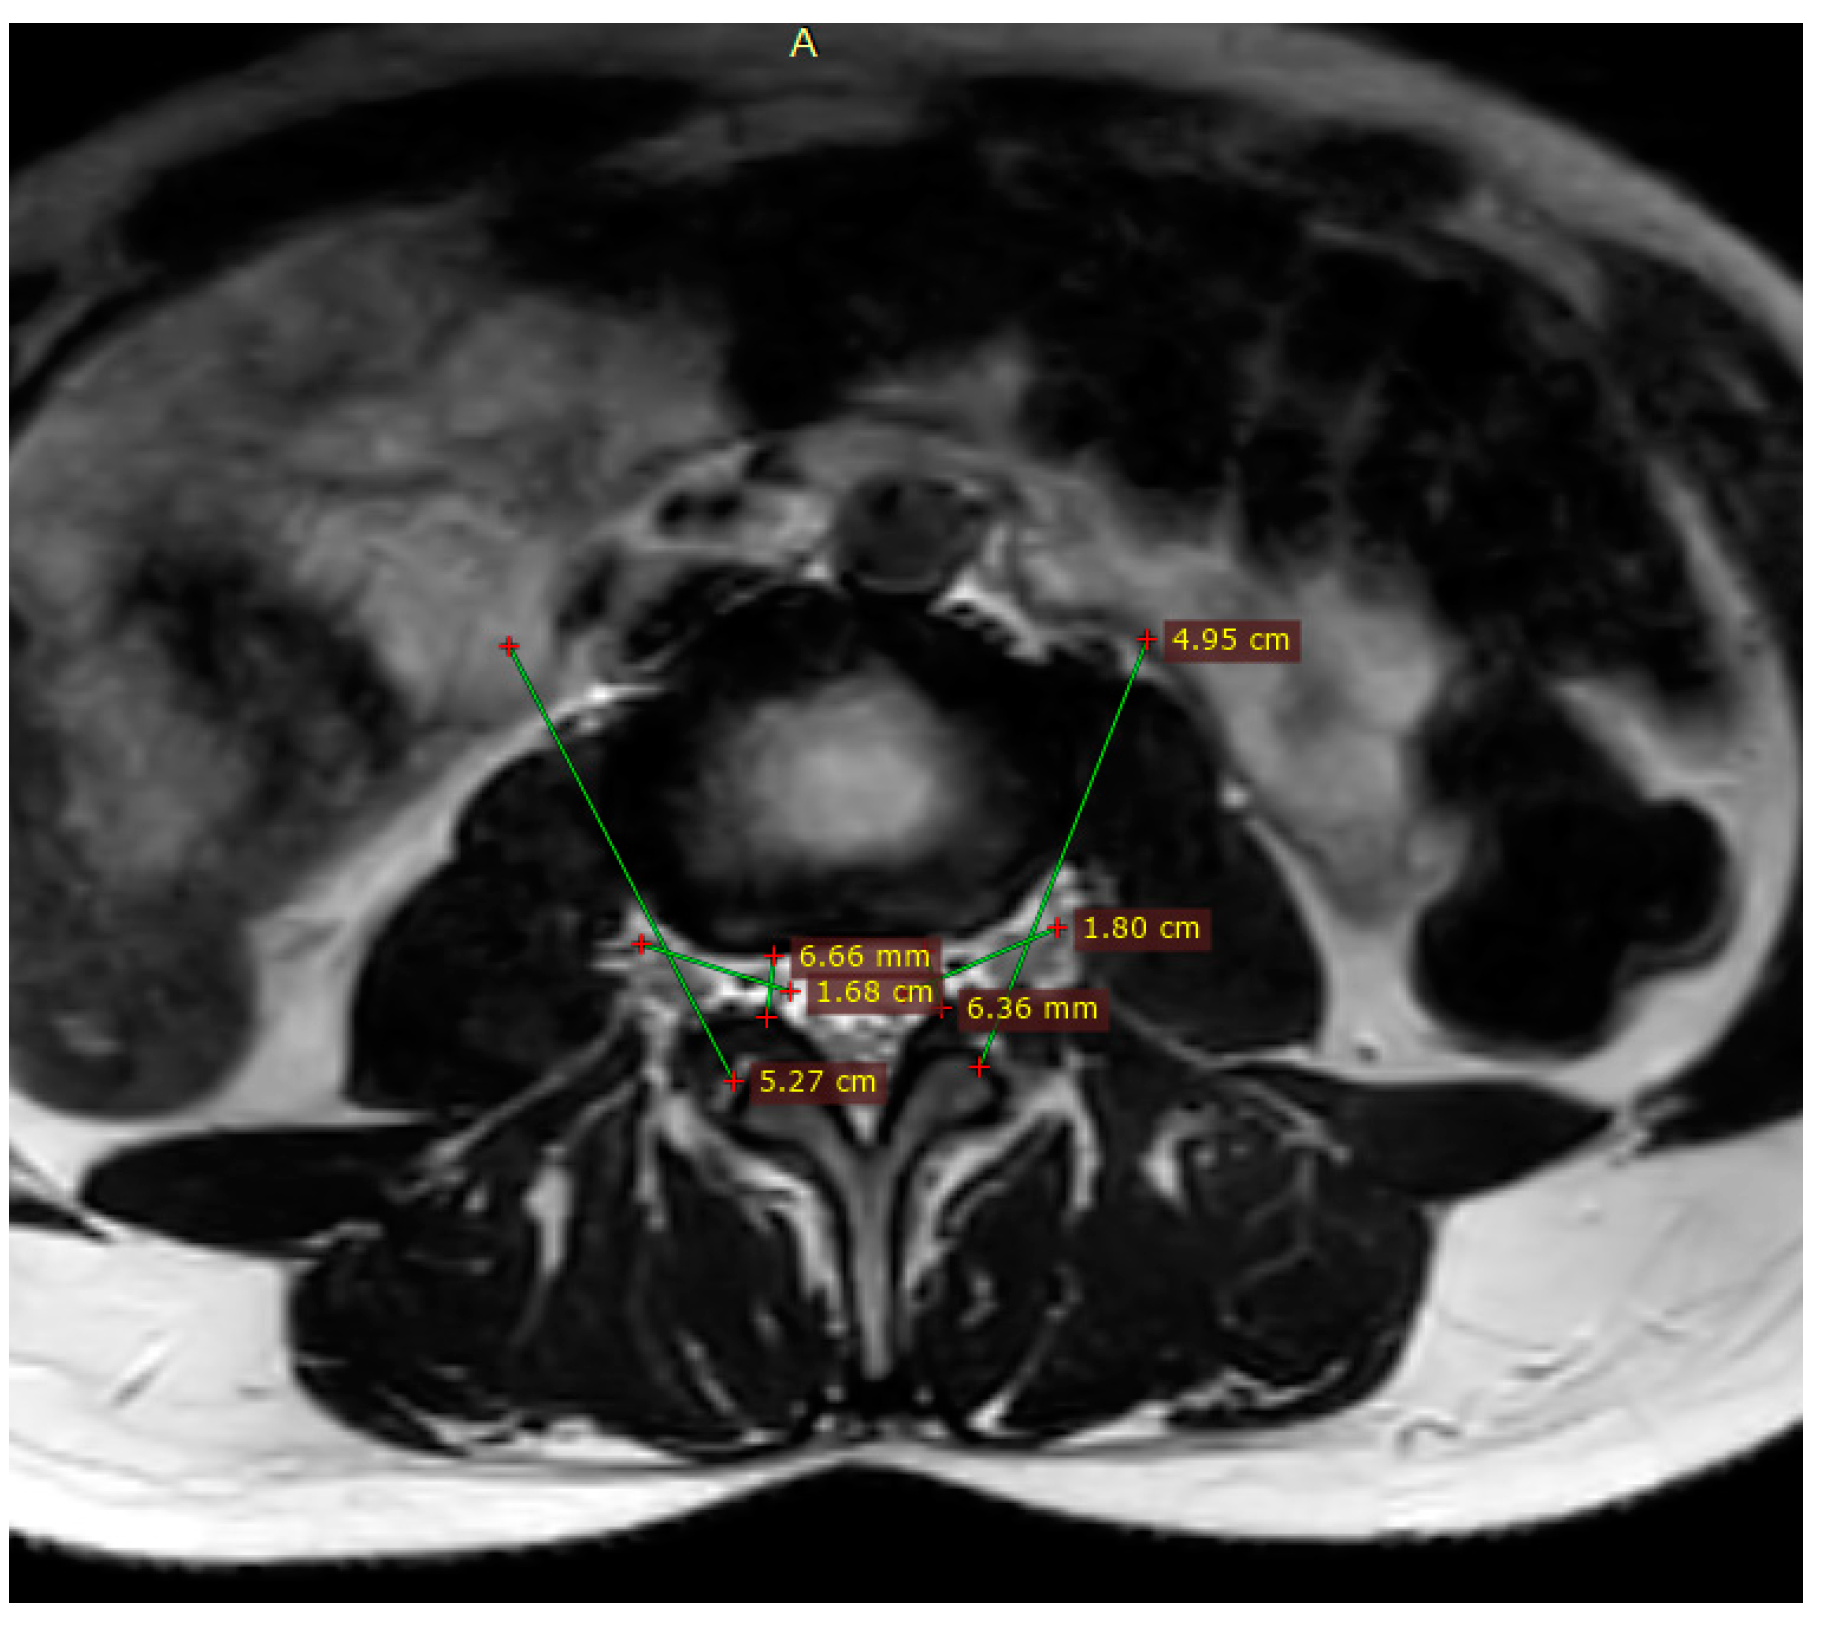

3.1. Volumetric Analysis of Lumbar Foramina